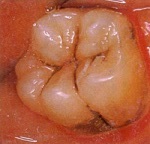

①虫歯があります

象牙質の虫歯(C2)

歯の鎧であるエナメル質を超えて、その中の象牙質に及んだ虫歯の状態です。 症状は、なにもない場合もあれば、冷たいものや甘いものがシミる、噛むと痛い、ものがはさまる、見た目が悪い、などが挙げられます。

虫歯をきれいに削り、コンポジットレジン修復、もしくは型取りをして、インレーと言われる金属やセラミックスのつめものを入れて治します。